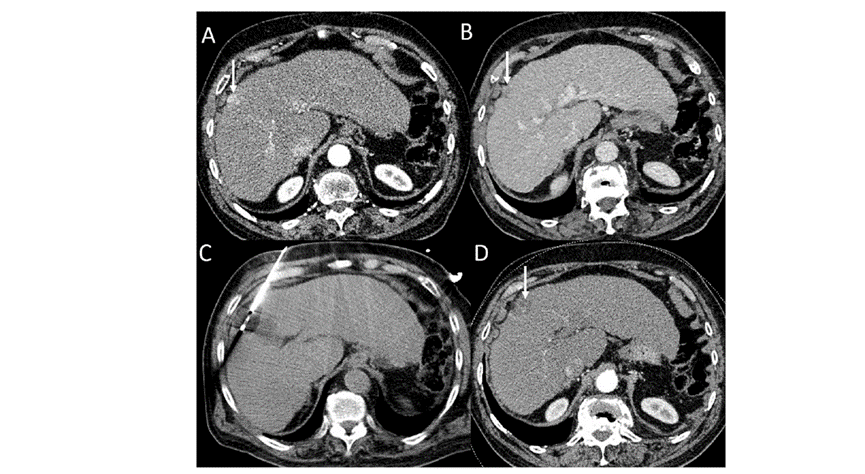

(A)动脉期CT图像显示有一个包膜下结节(箭头)。(C) 在手术过程中的CT显示一个冷冻探针位于病灶内。随访时间中位数为7个月(范围:3-12个月),随访期间患者无局部肿瘤进展或死亡。

(A)门静脉期 CT 图像显示胆囊附近有病变(箭头)。(D)消融手术后 1 个月CT 显示完全消融。

本研究中患者随访期间无局部肿瘤进展,无死亡病例,没有发现与手术相关的并发症。证实冷冻消融是一种有效的治疗方式,在技术上是可行和安全的。由于肝包膜下病变位置特殊,射频消融有出血及肿瘤种植的风险,可能会对邻近器官造成损伤,并且增加局部肿瘤进展的风险。近年来,冷冻消融术的应用逐渐广泛,有研究显示冷冻消融治疗具有明显优势,可治疗特殊部位的肝肿瘤。本研究的目的是评价冷冻消融治疗肝包膜下肿瘤的安全性和有效性。回顾性纳入2016年7月1日至2018年9月1日期间冷冻消融的57例患者。包括42例男性和15例女性,平均年龄为62.4岁(范围:48-82岁)。每个患者有1个或2个平均肿瘤尺寸为2.4cm的病变(范围:0.6-4.0cm)。所有患者均患有慢性肝病或肝硬化,并伴有乙型肝炎(n=52)、丙型肝炎(n=3)和其他肝炎(n=2)。根据肿瘤位置,在膈肌或肝脏下附近有18个病变(26.5%),胃或肠附近有9个病变(13.2%),腹壁附近有33个病变(48.5%),肾脏附近有8个病变(11.8%)。

完全消融率为97%(66/68);2名患者均接受了额外的冷冻消融,随后实现完全消融。平均随访期为 12.8 个月(范围:3-27 个月)。所有患者均接受影像复查(CT 或 MRI)。11个病灶(16.2%)检测到局部肿瘤进展,6、12和18个月时的累积局部肿瘤进展率分别为4%、8.2%和20.5%。8例出现远处肝内或肝外病变的患者接受经动脉化疗栓塞、经动脉化疗栓塞加射频消融治疗或全身化疗。

主要和次要并发症发生率分别为3.5%(2/57)和22.8%(13/57)。并发症主要表现为局部皮肤冻伤、中度气胸、发热,仅有少数患者接受治疗,多数患者自行恢复。所有患者能耐受围手术期疼痛,VAS 评分范围在 1-3 分之间(平均 1.65分)。3例患者术后疼痛加重,VAS评分达到4~5分,患者口服止痛药后逐渐缓解。所有患者术后1天血常规、白细胞计数均升高,血小板均有不同程度下降,但变化值均在正常范围内。肝功能1个月后逐渐恢复到正常水平。